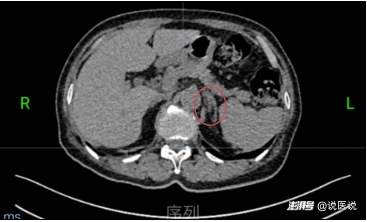

左側(cè)腎上腺增粗

這引起了醫(yī)生的高度警惕!耿阿姨長期服用硝苯地平控制血壓,該藥通常會使腎素升高,然而耿阿姨的腎素值過低,這一現(xiàn)象成為原醛癥的重要線索。隨后的腎上腺CT檢查也發(fā)現(xiàn)左側(cè)腎上腺增粗,進(jìn)一步支持了疑診。